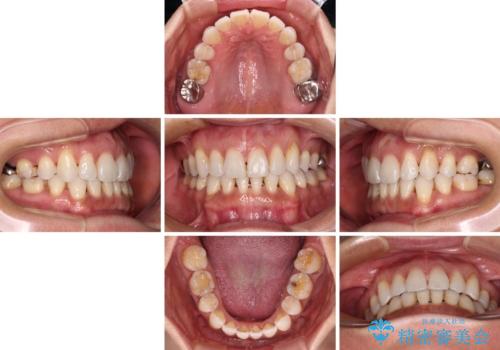

- 下顎前歯を中心に、以前行った矯正治療の後戻りが気になるとのことで来院された患者様です。

後戻りは軽度であったため、インビザライン・ライトにて治療を行うこととしました。

矯正治療後は、再度後戻りすることを極力回避するために、下顎前歯の舌側を細いワイヤーを用いて保定することとしました。